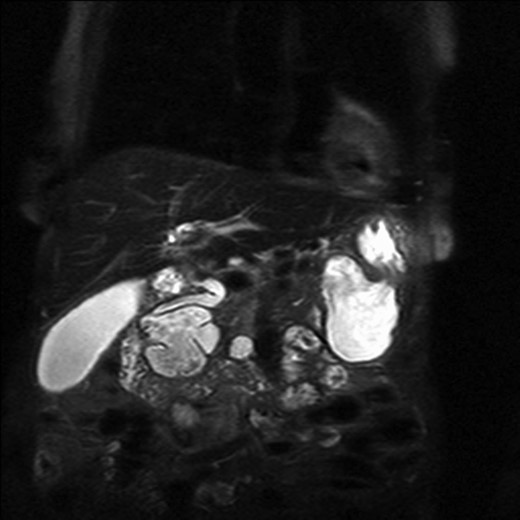

The patient underwent an MRCP which demonstrated mild distension of the gallbladder with several calculi. There was intra- and extra-hepatic biliary dilatation to the level of the ampulla. A very large fluid and air filled periampullary duodenal diverticulum measuring ~8 cm in the long axis was also noted (Figs 1–3). This finding was unchanged compared to a CT study from 6 months previously. The CBD was dilated to the level of this diverticulum and the cause of the patient’s biliary dilatation and obstruction. Interestingly, an unusual appearance to the kidneys was recorded with multiple microcystic changes in both kidneys, which is typically reported in patients with lithium induced renal disease. A gastroduodenoscopy revealed a large periduodenal diverticulum in D2 (Fig. 4).

Magnetic resonance imaging with a giant duodenal diverticulum.